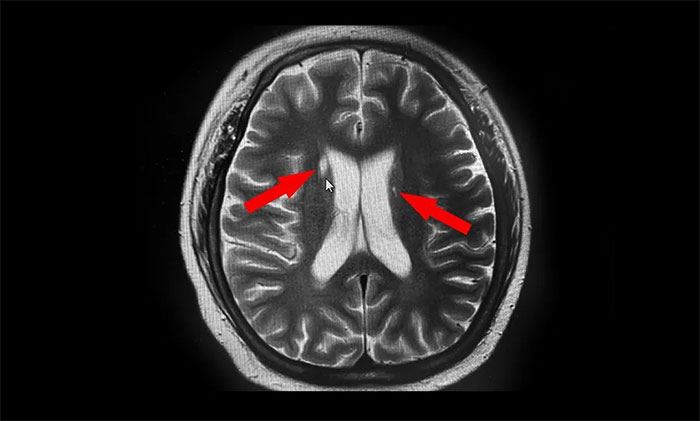

▲ 磁共振检查影像

磁共振检查示,阿泰右侧尾状核头部、左侧豆状核部都有高密度影,这两处与锥体外系各核团紧密联系,协同随意运动肌张力和姿势平衡,也参与复杂运动,因而考虑其为神经损伤后锥体外系症状表现。